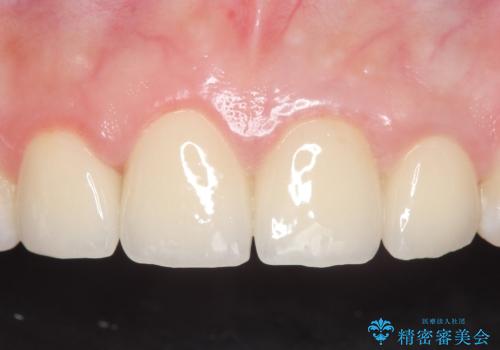

当院のセラミックインレーはemaxという強度と審美性に優れた材料を使用しています。

またプレス方式でインレーを製作しているため、削り出しで製作するCADCAMより優れた適合性も持ち合わせており、虫歯が再発しにくい修復物です。

セラミック治療の注意事項(リスク・副作用など)

- 天然歯を削ります

- 硬い素材は天然歯を傷つけてしまう場合があります

- かみ合わせや歯ぎしりが強すぎる方はセラミックが割れてしまう可能性があります

- 自費診療(保険適用外治療)となります